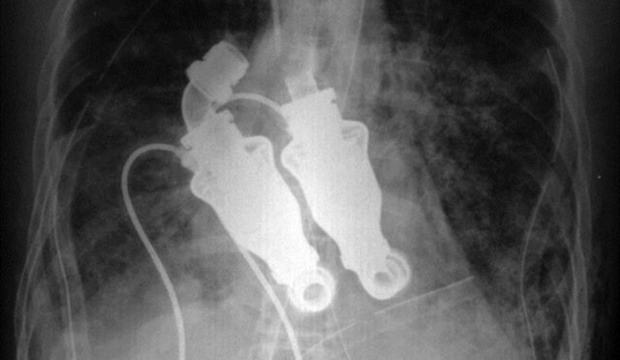

У американца Крэйга Льюиса нет сердца

В марте прошлого года 55-летний Крэйг Льюис (Craig Lewis) умирал от сердечной недостаточности, вызванной образованием в тканях его тела специфических белков, и даже установка кардиостимулятора не могла спасти ему жизнь.